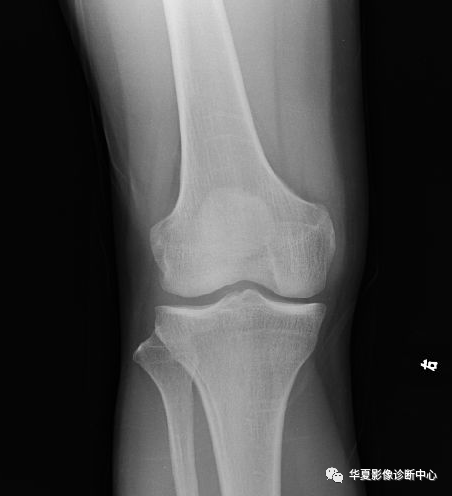

X-RAY

X线平片检查采用Kodak公司的CR成像系统,对患肢行正侧位投照.(图1-2)

图1